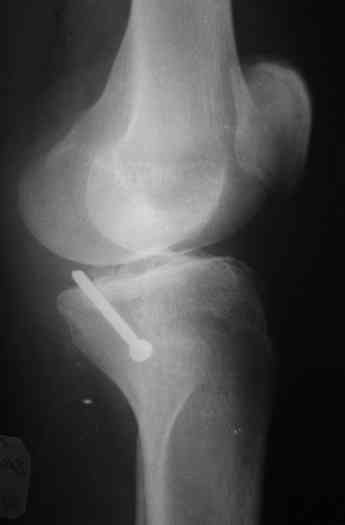

Операция завтра.По рекомендации наших зарубежных коллег выбрали заднемедиальный доступ с фиксацией пластиной и 2.7мм винтами.От Александра Николаевича уже получен наказ, о постоянном участии в операции фотоаппарата,постараюсь реализовать и ваш наказ тоже;-).Спасибо за высказанное мнение.

Операция из разряда травматологической "экзотики" прошла успешно. Доступ понравился:анатомичный, хорошая визуализация, удобно работать и оператору и ассистентам. Наложили пневможгут, но воспользовались им только на этапе ревизии сустава. Фрагмент развернулся на 90 град. на 2-ух "жгутах": медиально - сухожилие m.semitendinosus, латерально - задняя крестообразная связка. Мобилизовали,развернули и уложили на место без особого труда. Фиксировали отмоделированной 1/3-трубчатой пластиной. Мениск оказался неповрежден. Сустав стабилен. Обошлись без

иммобилизации, планируем начать ранние движения. Остальное на фото, дополнительно приложены корональные срезы КТ.

It is of course only butress, an artificial border of the plateau.

Прекрасный результат, прекрасная презентация и доступ хороший, и фиксация-Butress удалось на славу.